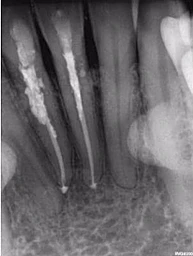

Một phụ nữ 54 tuổi với tiền sử chấn thương tới phòng khám với lý do răng 41 đau và áp xe gây khó khăn khi ăn nhai. Trên XQ 2 chiều thấy tổn thương tiêu ở răng 41 và áp xe ở răng 42 (Hình 1 và 2), rất khó để biết phạm vi nội tiêu theo hướng ngoài – trong. Tổn thương trông có vẻ rộng, nhưng có phá ra phía ngoài hay trong không? May mắn thay, phim chụp từ máy CS 8100 cho thấy nội tiêu chỉ nằm trong phạm vi ống tủy (hình 3 – 5), do đó tôi tự tin rằng điều trị tủy có thể giải quyết vấn đề của bệnh nhân, hai răng này sau đó được đặt Ca(OH)2 rồi trám bít (hình 6 và 7)

Hình 1: Phim XQ 2 chiều trước điều trị

Hình 2: XQ 2 chiều trước điều trị (ảnh chụp ở phòng khám khác